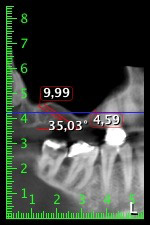

Etwa sechs Monate nach Extraktion der Zähne 16 und 14 wurde zur Planung und Risikominimierung eine digitale Volumentomografie (DVT, Planmeca) erstellt. Hierbei wurde deutlich, dass der Knochen sich nicht in der gewünschten Quantität regeneriert hat (Abb. 2 bis 7).

Abb. 2 bis 7: DVT mit stark reduziertem horizontalen Knochenangebot.

Um eine festsitzende Versorgung auf mindestens zwei Implantaten zu gewährleisten, ist eine Sinusbodenelevation sowohl in Regio 16 als auch in Regio 14 erforderlich. Da in diesem Fall das Restknochenangebot extrem gering ist, müsste ein verhältnismäßig großer Knochenaufbau durchgeführt werden. Große Knochenaufbauverfahren sind invasiv, mit einer höheren Patientenmorbidität verbunden, zeitintensiv und kostspielig. Die Vorhersagbarkeit der Behandlungsresultate ist geringer und das Misserfolgsrisiko höher. Vor dem Hintergrund dieser Nachteile, wurde die Patientin über eine herausnehmbare Alternative aufgeklärt, die sie jedoch konsequent ablehnte.

Um die Augmentation auf Regio 14 einzuschränken, wurde in Absprache mit der Patientin eine Schrägstellung des Implantats 16 nach dorso-kranial geplant (Abb. 8).